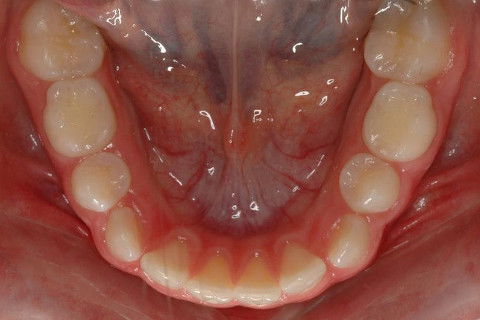

OCLUSAL INF. FINAL

OCLUSAL INF. INICIAL.